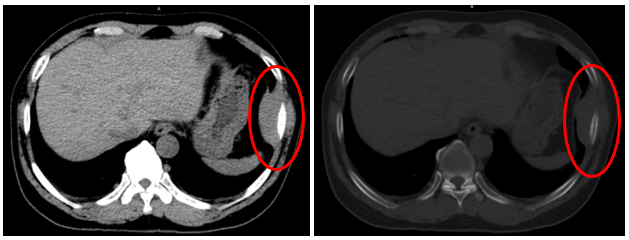

Hình 1: Hình ảnh chụp CT ở ngực - bụng có khối tỉ trọng tổ chức thành ngực trái ngang mức xương sườn 8, không xâm lấn vỏ xương lân cận ( mới xuất hiện so với trước đây).